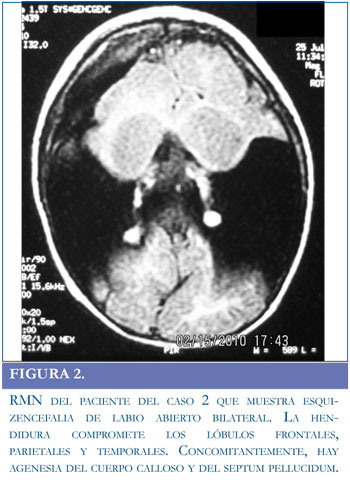

Paciente de 15 meses de edad. En la segunda semana de vida presentó una crisis convulsiva no especificada, razón por la cual le realizaron una TAC en la cual se definió el diagnóstico de esquizencefalia de labio abierto bilateral. La exploración física evidenció microcefalia y retardo global en el desarrollo psicomotor. No hubo controles prenatales. El paciente nació por cesárea a los siete meses de gestación debido a ruptura prematura de membranas ovulares y pesó 2.900 gr; presentaba circular de cordón. Se le realizó una resonancia magnética (RM) al año de edad, que mostró agenesia del cuerpo calloso y del septum pellucidum, además de la esquizencefalia (Figura 2).

Se reportan los estudios de dos pacientes con esquizencefalia de labio abierto, uno unilateral y otro bilateral. En ambos, los principales hallazgos son retardo psicomotor severo, epilepsia y cuadriparesia espástica; este último signo está asociado a la esquizencefalia bilateral, siendo infrecuente en la malformación unilateral (5, 10). Sin embargo, la cuadriparesia en el primer caso se explica debido a que la hendidura unilateral es muy severa y se acompaña de pérdida de parénquima cerebral en el hemisferio contralateral. Sólo el primer paciente manifestó dilatación del sistema ventricular. El segundo paciente presentó microcefalia, agenesia

del cuerpo calloso y del septum pellucidum. Mejia et al reportaron una incidencia de agenesia del septum pellucidum del 40%, malformaciones del cuerpo calloso en el 22,9% y microcefalia en 31,4% de los pacientes con esquizencefalia (10).